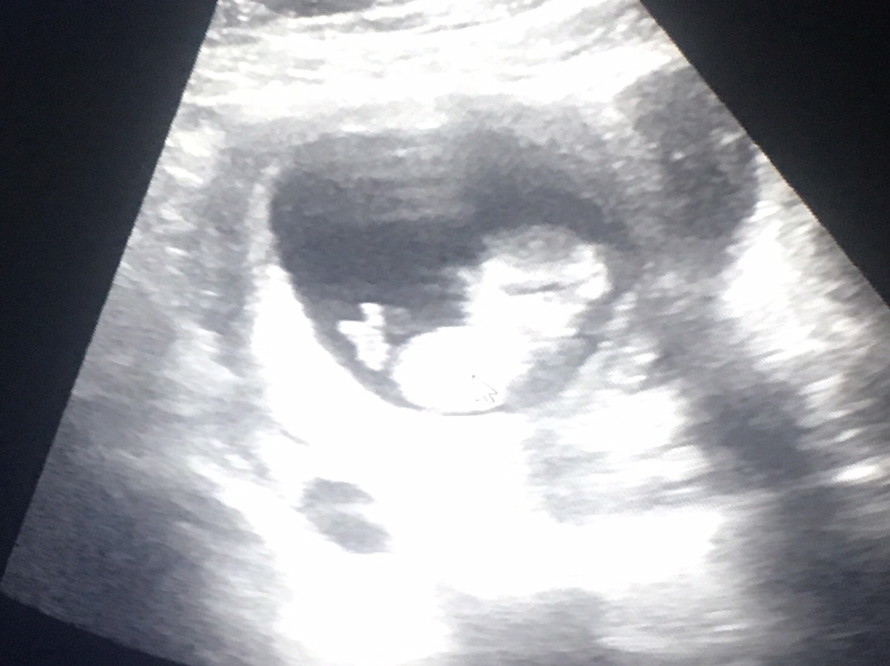

12Wเหมือนกันจ้า